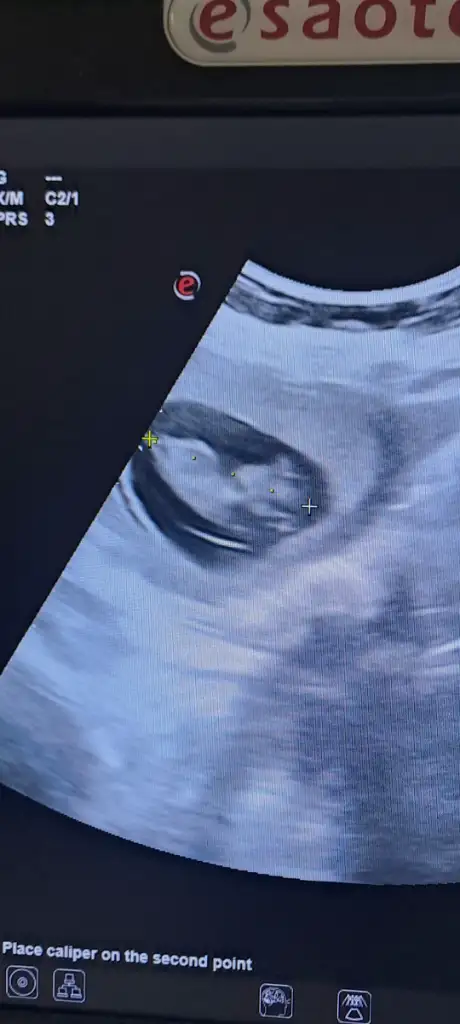

Kız hissettimMerhabalar rica etsem bana da tahminde bulunabilirmisiniz 11+4 haftalık

Erkek hissettimBize de tahminde bulunur musunuz11 haftalık